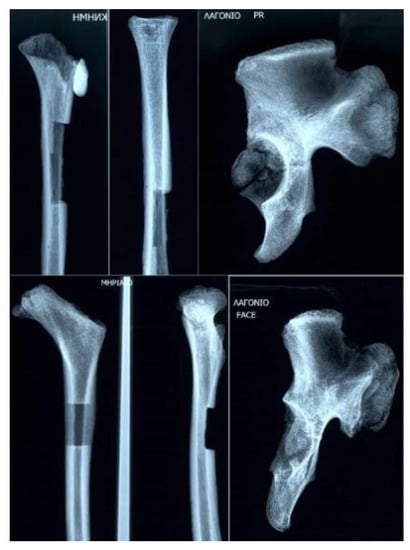

Macroscopical observation of the tibia and femur showed strong cortices in both bones, which revealed the mode of loading. This implied possibly a strong musculature of the studied specimen. Moreover, hypoplastic eminences in the tibia and possibly subsequent hypoplasia of the cruciate ligaments were visible.

3.3. Paleopathology

No pathological lesions were recorded, macroscopically, except for a slight porosis in the bregmatic area. The findings from the endoscopic analysis did not show any intra vitam lesions, but severe diagenesis was diagnosed in almost all areas of the endocranium and the orbital laminae. However, two noteworthy findings were remarked in the X-rays. In the X-ray of the long bones, Harris lines, or growth arrest lines, were visible (Figure 4). Furthermore, in the skull X-ray, a hair-on-end pattern was noted, especially around the lambda point, along with a widening of the diploic space (Figure 5). Signs of pitting edema were suggested around the bregmatic areas of the skull.

Figure 4. X-ray of the long and pelvic bones.